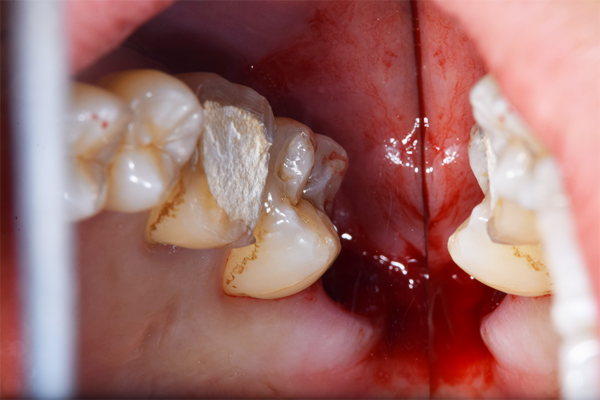

上顎はしっかり親知らずがはえています。下顎は右(青)はしっかりはえていますが、虫歯になっています。下顎の左(赤)は斜めにはえています。またこちらも虫歯になっています。

親知らずは、のどに近いですし、頬っぺたもありますので、なかなか磨くのが難しいですね。そのため、虫歯になりやすい傾向にあります。また、プラーク(歯垢)除去がしずらいため、親知らずの周りの歯茎が腫れたり、出血しやすくなります。